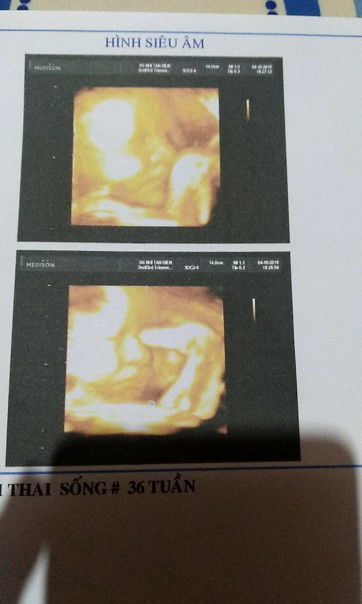

ai tot vía vô chúc e cai cho e di đẻ di nao

be cưng

e cua me 37w